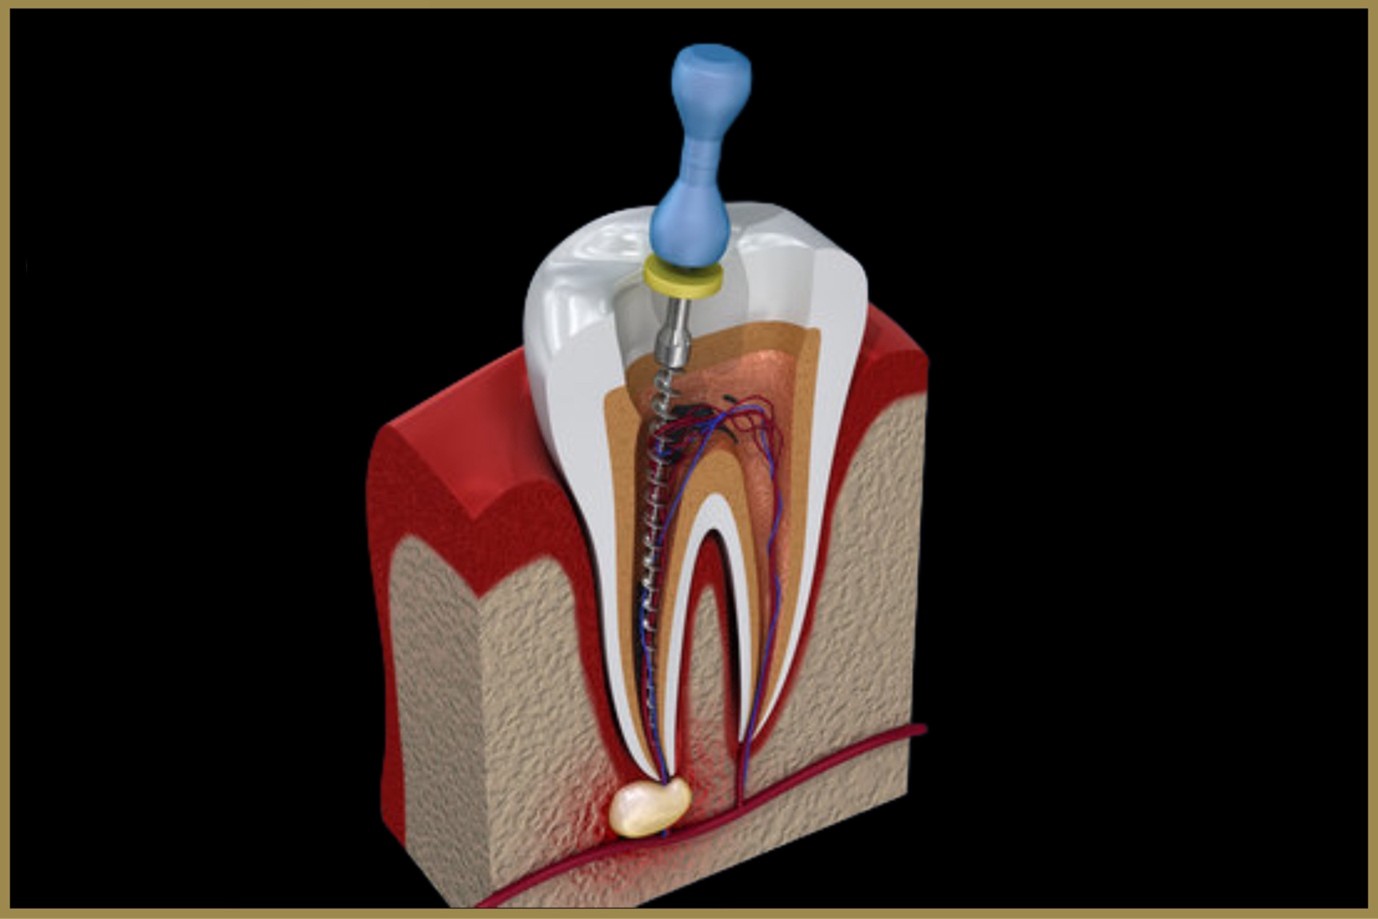

A dental crown is a cap placed over a weakened or treated tooth (such as after a Root Canal Treatment) to protect it and restore its function. A bridge replaces one or more missing teeth by anchoring an artificial tooth to adjacent natural teeth or implants. Both options are designed to look, feel, and function like natural teeth.

When are Crowns & Bridges recommended?

After Root Canal Treatment for added protection

To restore broken, cracked, or severely worn teeth

To replace missing teeth for a complete smile

For cosmetic improvement of discolored or misshapen teeth

To strengthen teeth with large fillings

How the procedure works:

Examination & Preparation – Tooth reshaping and impressions taken with advanced digital tools

Temporary Protection – A temporary crown or bridge is placed for comfort

Custom Creation – Lab-crafted restoration designed to match natural color and shape

Final Placement – Crown or bridge securely fitted and polished for a flawless finish

Benefits of Crowns & Bridges

Restores Strength & Function – Enables chewing and speaking with ease

Natural Appearance – Matches surrounding teeth for a seamless look

Long-Lasting Durability – With proper care, they can last many years

Prevents Shifting – Bridges maintain proper alignment by filling gaps

Boosts Confidence – Improves both aesthetics and oral health

At Elite Dental Care, we use advanced materials and precision techniques to ensure crowns and bridges that are durable, comfortable, and indistinguishable from natural teeth—helping you smile with confidence again.